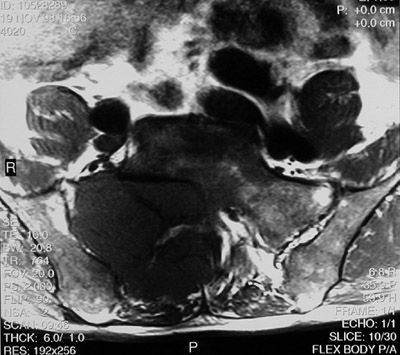

The large destructive mass seen here with oblique T1 weighted MRI scan above and T2 weighted scan below is a chordoma. It is arising in the sacrum and extending to the right.